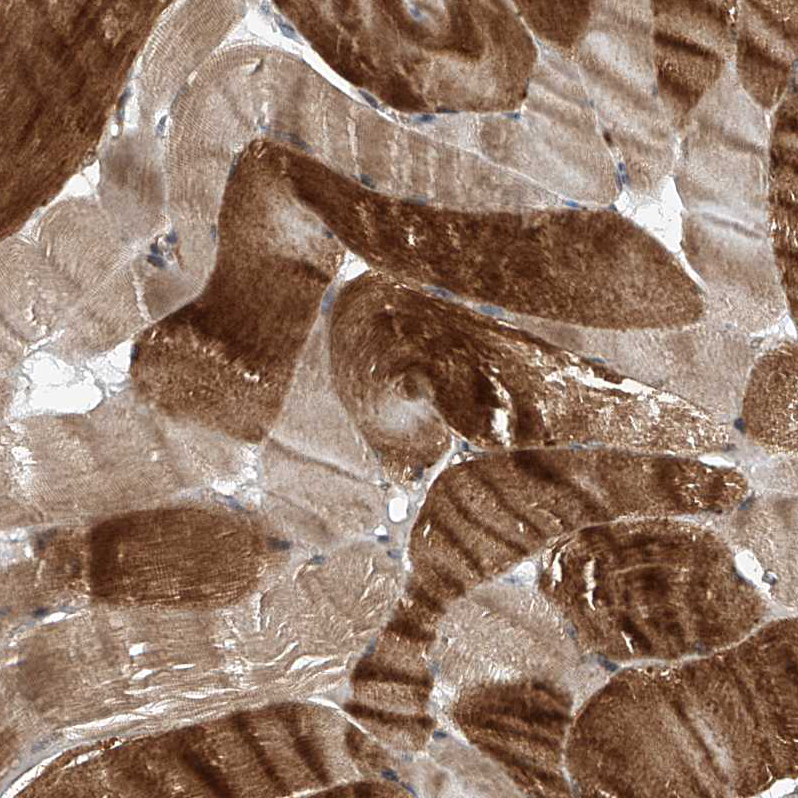

Immunohistochemical staining of human testis shows strong cytoplasmic positivity in cells in seminiferous ducts.